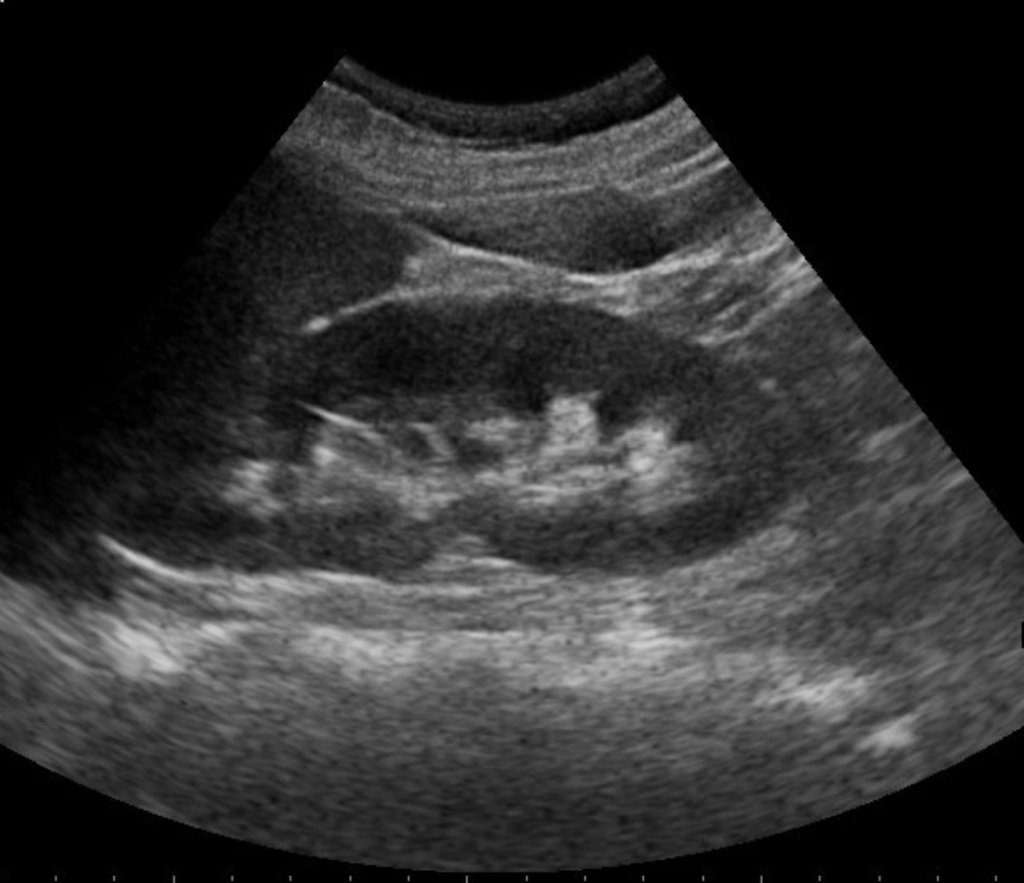

Badanie USG nerek jest jednym z najczęściej wykonywanych badań obrazowych w diagnostyce chorób układu moczowego, w tym kamicy nerkowej. Choć samo badanie jest szybkie i bezbolesne, odpowiednie przygotowanie pacjenta ma kluczowe znaczenie dla jakości obrazu i wiarygodności wyniku. W tym artykule wyjaśniamy krok po kroku, jak prawidłowo przygotować się do USG nerek.

Tak, szczególnie kamienie większe niż 3–4 mm, zwłaszcza w obrębie nerki lub miedniczki.